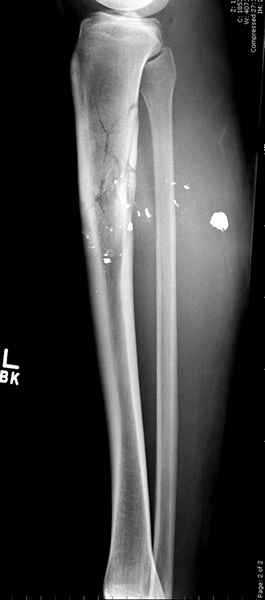

1 неполный перелом большеберцовой кости перкутанная пластина

Оставленные во время обработки нетронутые фрагменты со временем образуют основу костной мозоли. При недостаточности костной мозоли в последующем дефект восполнялся за счет аутопластики из минимального доступа.

Внутреннее кровоснабжение канала "запретная зона Илизарова" восстанавливалось в течение двух с половиной недель без осложнении после восстановления непрерывности канала.